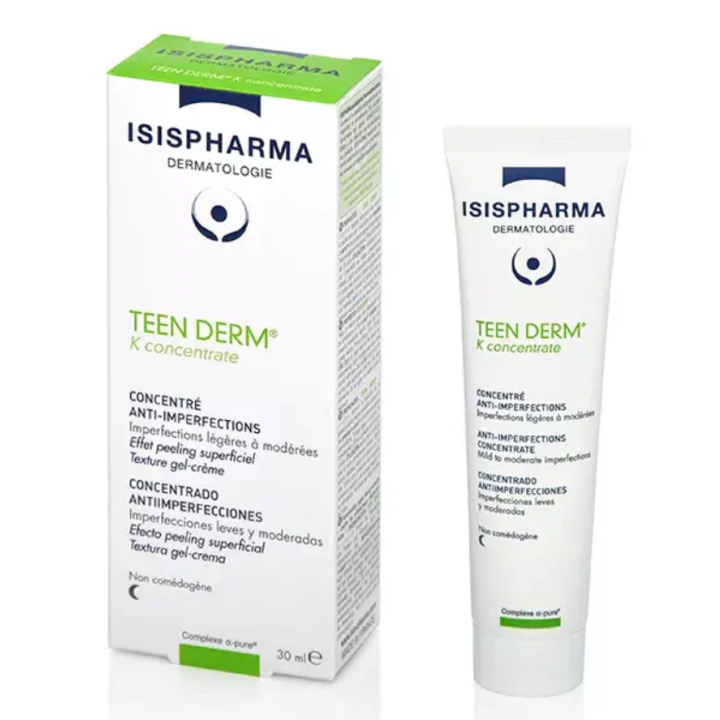

Véritable soin SOS grâce à sa forte concentration (dose maximale autorisée en cosmétique), il réduit les boutons naissants ou installés sur le visage en seulement quelques jours. | Isispharma Teen Derm K Concentrate Concentré Anti-Imperfections 30ml est un soin de nuit qui s'adresse aux peaux mixtes à grasses afin de diminuer les imperfections et réguler l'excès de sébum. | Le soin réparateur apaisant boréade R noviderm ACM hydrate, répare et apaise les peaux irritées et desséchées. | Effaclat duo (+) unifiant soin teinté La Roche-posay est un soin teinté anti-imperfections correcteur désincrustant anti-marques. | Ce soin global « tout en un » favorise l’élimination des imperfections cutanées, unifie naturellement le teint et limite l’apparition des marques liées au soleil. | Le Gel SOS asséchant HYSEAC est un soin local SOS "effet patch invisible" à utiliser tout au long de la journée. | Hyséac Sérum peau neuve Booster anti-imperfections 30 ml est un sérum anti-imperfections pour les peaux adultes à tendance acnéique. |